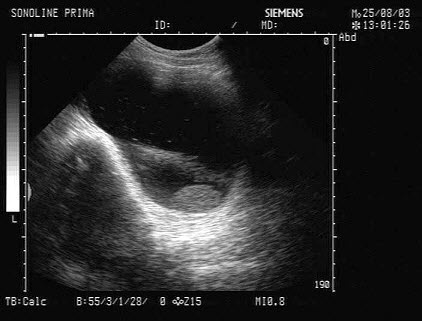

某患者自诉乳腺可触及一包块,光滑可移动,超声图像如图,诊断为()

A.纤维瘤

B.囊肿

C.乳腺癌

D.小叶增生

E.乳腺导管扩张